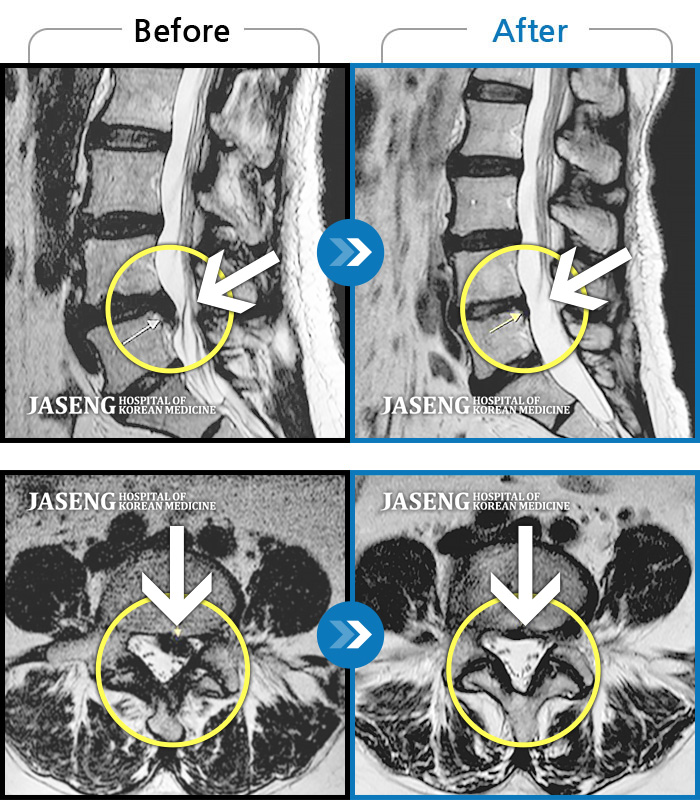

허리디스크

많이 본 사례

강남 · 강만호 원장

허리통증이 심해서 숙이기 어렵고 차에서 내리기 힘들었습니다.

촬영시기

2021.01.06 ~ 2025.03.10

2025.03.20

조회수 13,020